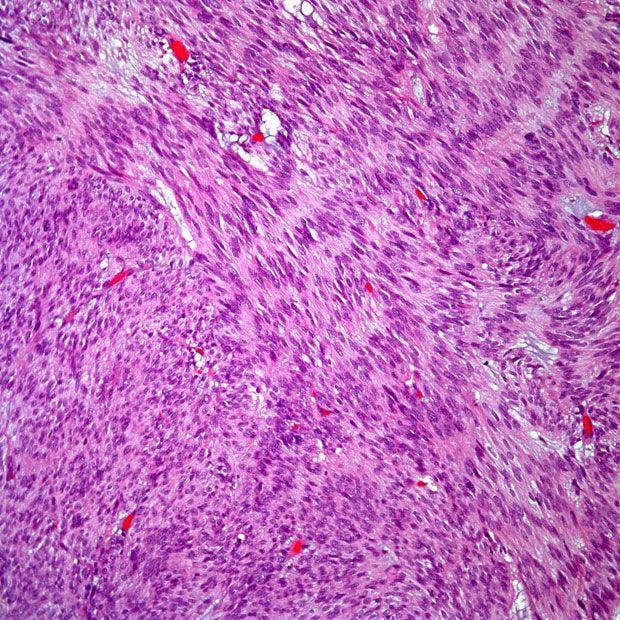

Микрофотографии гистологии глиобластомы головного мозга